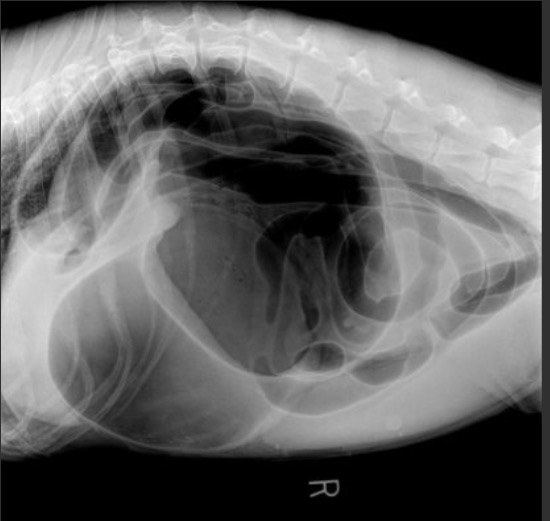

It was the classic presentation of a gastric torsion, a twisting of the stomach, that had the habit to occur nearly exclusively in the evening or at night in older, large breed dogs.

With the blood supply virtually cut off to some vital internal organs, this dog was in serious trouble and if its owners would have waited until the next morning, euthanasia would have been the only option left, if the dog would still have been alive by then….

Here aggressive fluid therapy and immediate surgery was the only sensible solution, and once treatment consent had been given by the distraught owners despite a guarded prognosis, the whole team focused on just this patient.

I/v lines where established and with the help of pressure cuffs, fluid was flooding into the veins of this patient. A few moments later the dog was asleep and out of pain and a couple of clippers prepared the abdomen for surgery.

If done in time, this can be an extremely rewarding procedure.

Once the abdominal cavity had been opened and a stomach tube passed to release gas and remaining stomach content, the stomach lining and the surrounding organs were inspected and found to be not too compromised, before the stomach was then attached in the correct position to the right chest wall.

Once that had been done, the wound was closed and the patient woke up from the anaesthesia. But even then, the battle was far from over, as a fair number of patients succumb in the following 24 hours due to complications caused by the disruption the condition had caused to the whole system.